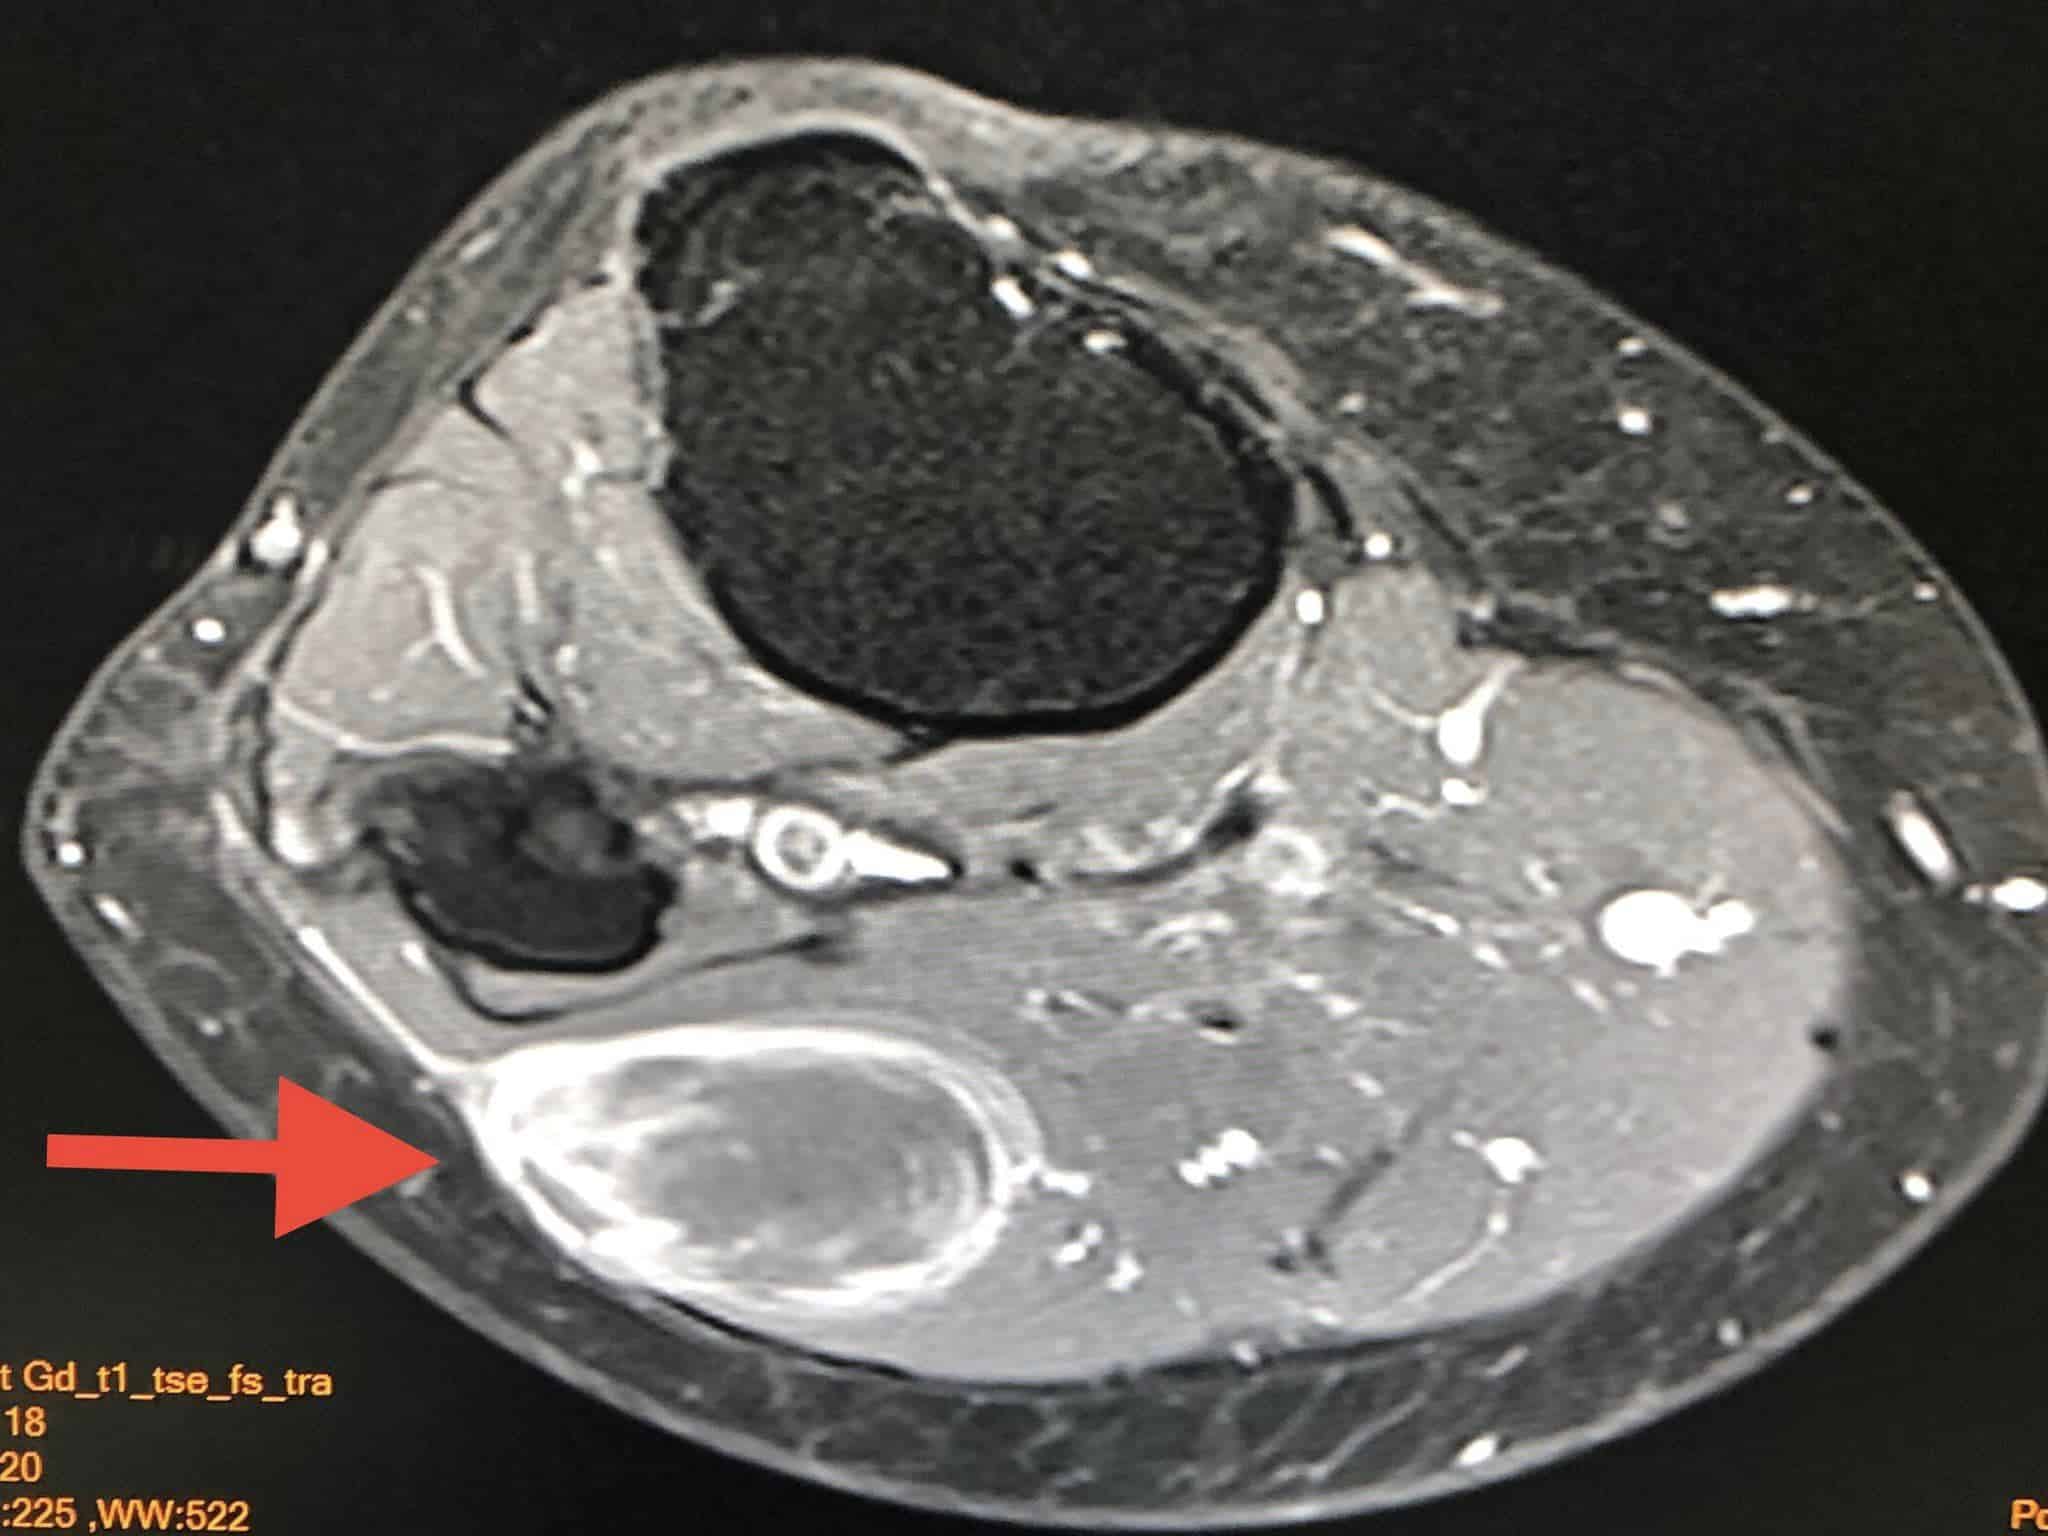

ผู้ป่วยหญิงอายุ 61 ปี ปกติแข็งแรงดี คลำได้ก้อนที่ขาใต้หัวเข่าข้างขวาด้านนอกขนาด 5 เซนติเมตร (ดูรูป) ก้อนนูนแข็ง ขยับก้อนได้ ค่อยๆโตขึ้น ไม่เจ็บ เดือนมีนาคม 2565 ทำ MRI ตรวจคลื่นแม่เหล็กไฟฟ้า พบก้อนขนาด 3.5 x 2.2 x 5.1 เซนติเมตร อยู่ชั้นใต้ผิวหนังติดกับกล้ามเนื้อของขา สงสัยมะเร็งเนื้อเยื่ออ่อน (soft tissue sarcoma) (ดูรูป)

ผ่าตัดกว้างเอาก้อนเนื้อที่ขาออกเมื่อเดือนเมษายน 2565 ส่งตรวจพยาธิวิทยาเป็น Myxofibrosarcoma มะเร็งของเนื้อเยื่อเกี่ยวพัน ขนาด 4.8 x 4.2 x 6 เซนติเมตร เกรดสูงระดับ 3 ไม่พบมะเร็งที่ขอบรอบๆก้อนเนื้อที่ตัดออก แสดงว่าแพทย์ผ่าตัดเอาเนื้องอกออกได้ทั้งหมด